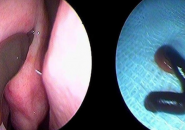

PHÁT HIỆN CON VẮT TRONG HỐC MŨI CÔ GÁI

Vừa qua tại Thái Nguyên, Một cô gái đi khám vì chảy máu cam thường xuyên, qua quá trình thăm khám bác sĩ đã phát hiện một con vắt dài 3cm được phát hiện trong...